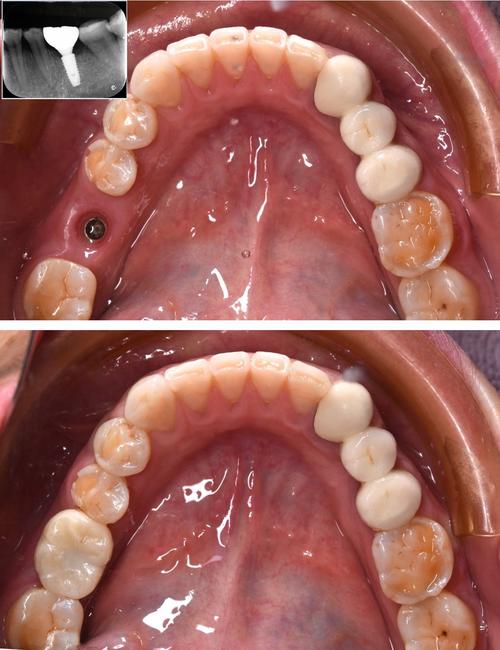

植入种植体,确保初期稳定性

备洞完成后,将选定的种植体(通常为纯钛或钛合金材质,表面经喷砂酸蚀处理以增加骨结合面积)用植入器或手动扳手缓慢旋入窝洞中,植入过程中需注意:

- 方向控制:严格按照术前CBCT规划的植入角度进行,避免种植体偏向邻牙、神经管或上颌窦。

- 深度控制:种植体顶部应与牙槽骨表面平齐,或根据修复需求略微低于骨面(埋入式种植),为后续基台安装留出空间。

- 初期稳定性:种植体植入后需具备良好的“初期稳定性”(即植入瞬时的机械稳定性),这是骨结合的前提,可通过叩诊种植体(无松动感)或植入扭矩监测(通常植入扭矩>35N·cm)判断,若稳定性不足,可能需选择更粗的种植体或进行骨增量处理。

种植体植入后,需经历“骨结合期”(3-6个月),期间种植体与牙槽骨逐渐融合,期间需避免种植体承受过大咬合力(如不用患侧咀嚼、不啃咬硬物),骨结合完成后,需安装基台(连接种植体与牙冠的中间结构),再取模制作牙冠(全瓷冠、烤瓷冠等),最终完成修复。